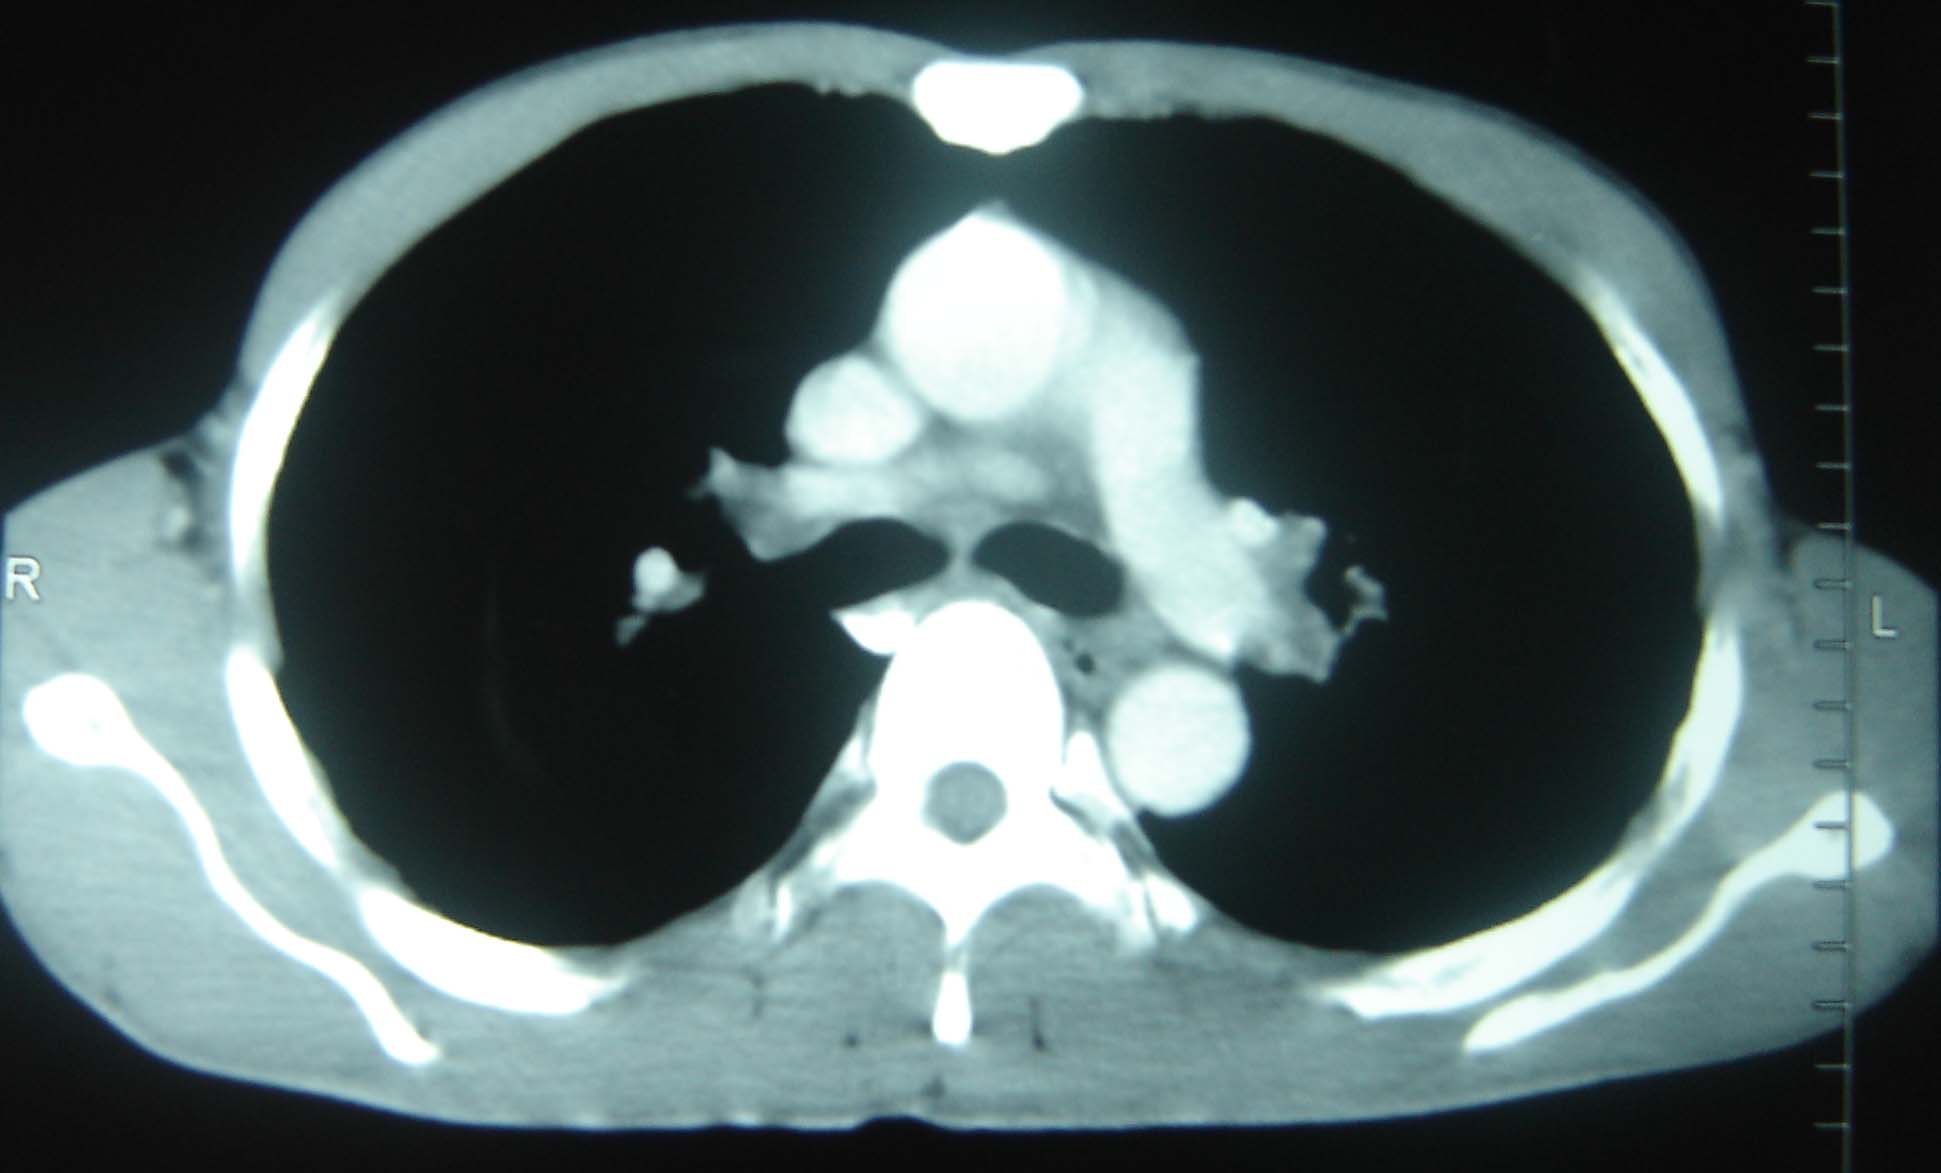

标题: CT25321:两肺多发结节 请会诊 [打印本页]

标题: CT25321:两肺多发结节 请会诊

男 、43岁,咳嗽胸痛,装修工,平时接触粉尘较多,有吸烟史10多年,纤维支气管镜检查未发现异常,胃镜、腹部b超检查亦未发现异常,颈部淋巴结活检未发现肿瘤细胞。

1)考虑双肺及胸膜多发性转移瘤。2)肺气肿。